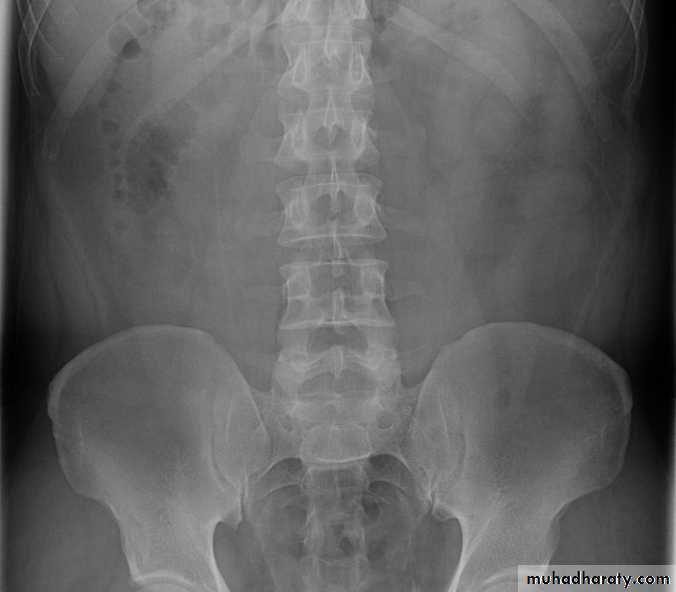

-Over 90% of calculi are radiopaque on plain films and virtually all on CT as very sensitive for detection of calculi, even those that appear radiolucent on plain film.-Most of these stones are a mixture of calcium oxalate and phosphate.

• Ddgx of stone on KUB :

• 1. Gall stone• 2. calfied LN , cartilage ,fibroid,

• 3. Phlebolith: round, lucent centre.